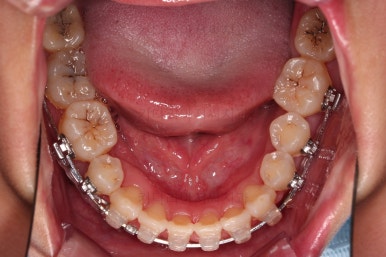

4. 마무리

위아래 좌우 치아가 없는 위치가 모두 달랐지만 교합도 잘 구성했고요.

아무래도 좌우 치아 크기들이 다르다 보니(뽑은 치아가 다르니) 중앙선은 100% 일직선은 안맞더라도 매우 정상 범주로 마무리를 할 수 있었습니다.

특히 어금니에 보이던 충치도 깔끔하게 마무리 했고요.

이제 부산교정치과 전후 비교해 보겠습니다.

치아배열, 틈새, 교합, 중앙선, 입매, 심지어 충치까지 깔끔히 잘 마무리 되었습니다.

그래도 치료적으로 매우 만족스러운 치료였습니다.

앞으로 다시 틈새가 벌어지지 않을지 유지 체크가 매우 중요한 상황이 되겠네요.

이상 다수 치아 결손 및 돌출, 치아 사이 틈새 등의 복합적인 문제점을 임플란트 없이 교정치료만 마무리를 한 부산교정치과 치료사례였습니다.